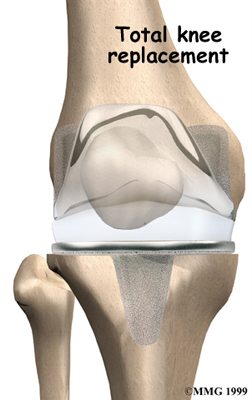

Artificial Knee Replacement

An artificial knee replacement is the ultimate solution for advanced knee OA.

Surgeons prefer not to put a new knee joint in patients younger than 60. This is because younger patients are generally more active and might put too much stress on the joint, causing it to loosen or even crack. A revision surgery to replace a damaged prosthesis is harder to do, has more possible complications, and is usually less successful than a first-time joint replacement surgery.

Related Document: FYZICAL Frisco Stonebrook's Guide to Artificial Joint Replacement of the Knee